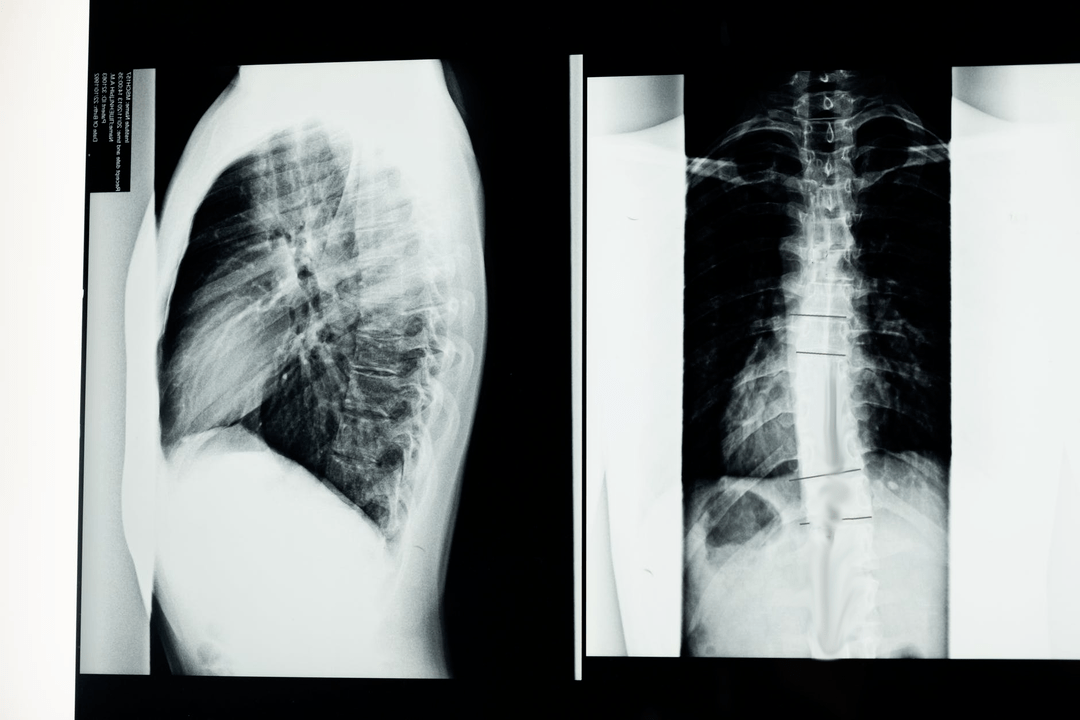

Vor Beginn diagnostischer Untersuchungen erhebt der Neurologe die Krankengeschichte des Patienten und untersucht sorgfältig seine Beschwerden. Osteochondrose weist bei einigen anderen Krankheiten gemeinsame Symptome auf, daher ist es wichtig, Pathologien unterscheiden zu können. Röntgenuntersuchungen helfen, die Diagnose einer Osteochondrose zu bestätigen: Radiographie, Myelographie und Computertomographie.

Mit einer Untersuchungsröntgenaufnahme können Sie ein Röntgenbild der Wirbelsäule oder eines Abschnitts davon anfertigen. Auf diese Weise kann der Arzt den von der Erkrankung betroffenen Ort bestimmen. Zur Verdeutlichung erklären wir Ihnen, wie eine Osteochondrose mittels Röntgen festgestellt werden kann: Das Bild zeigt eine Verengung der Bandscheibe, das Vorhandensein von Knochenwucherungen (Osteophyten) oder eine Formveränderung des Wirbelsäulensegments.